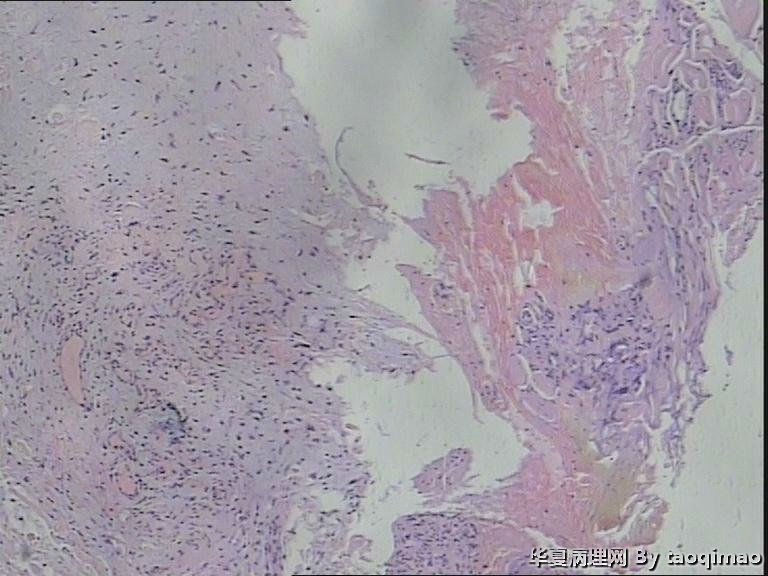

胸壁肿物

结节性筋膜炎+神经节样细胞+肌肉浸润=增生性肌炎。

考虑:坏死性筋膜炎,结节性筋膜炎,粘液瘤,脂肪肉瘤,神经纤维瘤等。

粗略看了下,对软组织病变不是很在行,初步印象是增生性肌炎,几个图像里小血管内皮肿胀,周围炎细胞浸润,结合临床除外血管炎或者自身免疫相关疾病。

男,54岁,右侧胸壁肿物发现1月余,取材:灰白色不规则组织一块2*1.7*0.5cm,剖面实性灰白色,质韧。